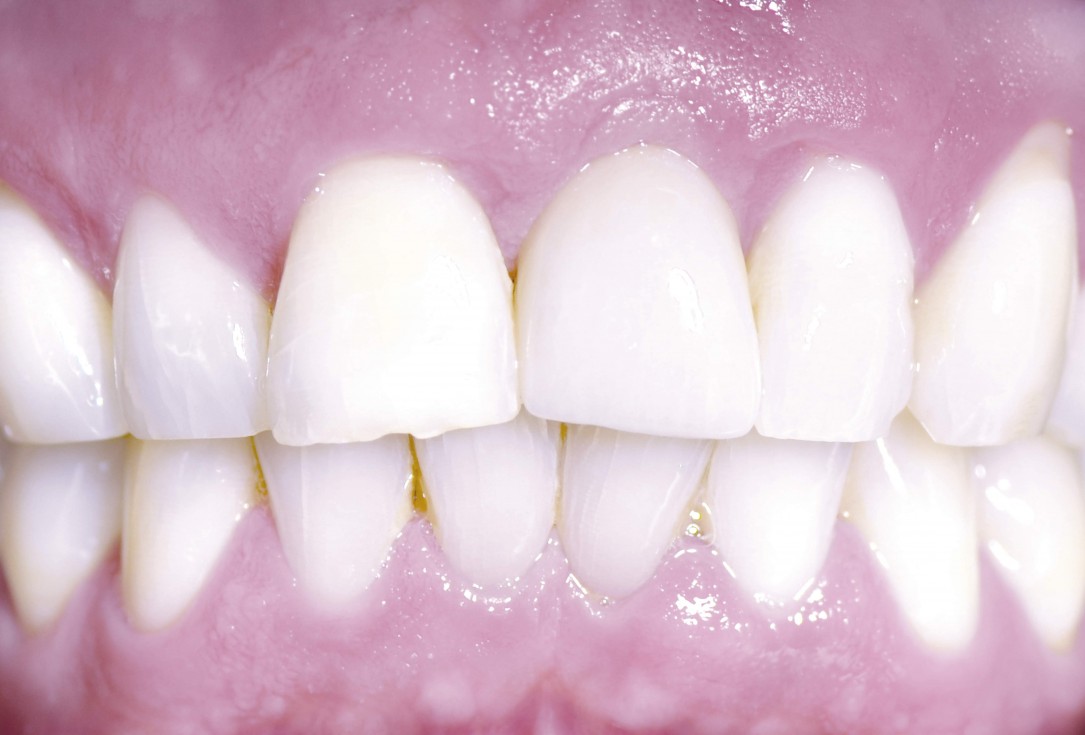

18/18 - Prosthetics 1 year after uncovering the implant

Block augmentation with maxgraft® and cerabone® – PD Dr. Dr. F. Kloss